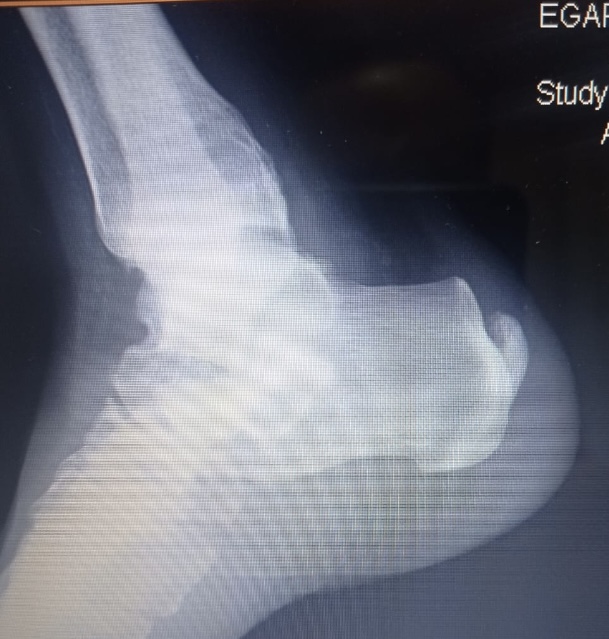

Fracturas de Calcáneo

Las fracturas de calcáneo (hueso del talón) son lesiones frecuentes por caídas de una altura o accidentes de tráfico.

Cursa con gran inflamación y dolor que imposibilita el apoyo del pie y caminar.

La reconstrucción de estas fracturas es compleja y no exenta de complicaciones, por lo que es recomendable sean tratadas por cirujanos expertos. En nuestra Unidad tenemos amplia experiencia en el tratamiento de estas lesiones, tanto en la reconstrucción de las lesiones agudas como en la de las secuelas

Las radiografías y sobretodo el TAC ayudan a clarificar el tipo de fractura, el desplazamiento de los fragmentos óseos y el tratamiento a seguir.

El tratamiento intentará restablecer la anatomía, siendo para ello necesaria la intervención quirúrgica y la reconstrucción con placas específicas y tornillos.